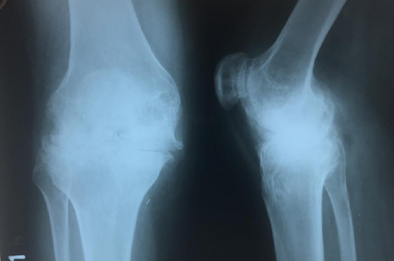

Knee Replacement